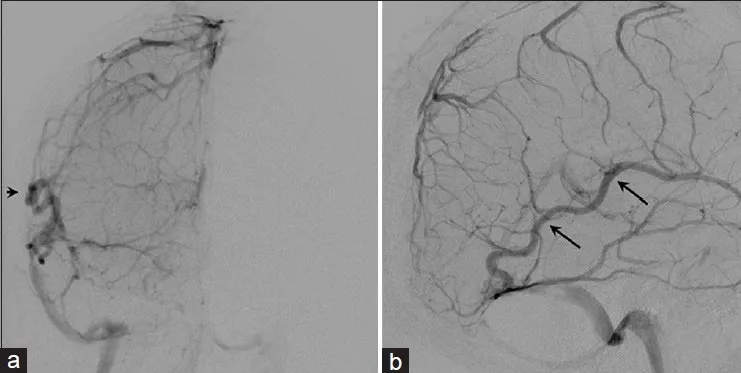

肿瘤经颅骨侵犯至枕部头皮及真皮层。脑血管造影显示上矢状窦、窦汇及横窦近端部分节段血流消失(图2)。深部静脉经枕窦引流(图2),皮质静脉经增粗的Labbe静脉引流(图3)。肿瘤血供丰富,主要动脉供血来自颈外动脉的脑膜支及小脑后下动脉(图4)。术前采用弹簧圈及聚乙烯醇颗粒对颈外动脉的肿瘤供血动脉进行了栓塞治疗(图4)。本病例的鉴别诊断包括血管外皮细胞瘤、脑膜瘤、肉瘤及隐匿性恶性肿瘤。

图3.右侧颈内动脉注射静脉期脑血管造影前后位(a)与侧位(b)观。皮质静脉经扩张的Labbe静脉引流(黑色箭头)